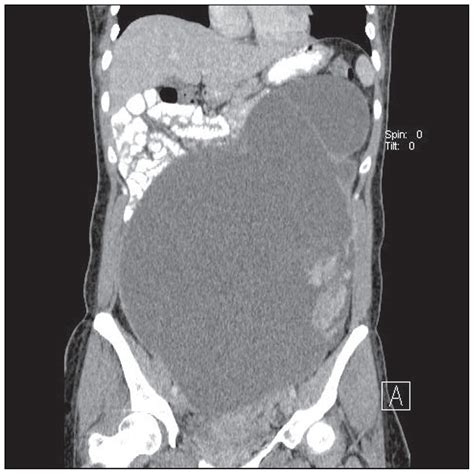

Although an abdominal CT normal result is ideal, it's also important to be aware of the common abnormalities that can be detected by these scans. Some of these abnormalities include:

• Tumors and Cysts: Abnormal growths or fluid-filled sacs that can be benign or malignant.

• Inflammation and Infection: Conditions such as appendicitis, diverticulitis, or abscesses.

• Organ Damage: Injuries or diseases affecting the liver, kidneys, or other organs.

• Blockages: Obstructions in the intestines or other digestive structures.

• Blood Vessel Issues: Problems with blood vessels, such as aneurysms or blood clots.